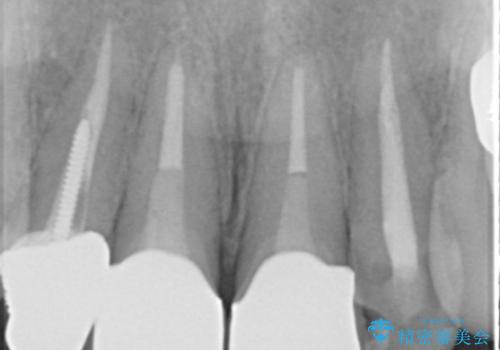

- 過去に他院で治療した前歯が取れたとの事で来院。

被せ物だけでなく中の土台まで取れていました。

歯の根っこのお掃除(根管治療(保険))を行い、土台を立ててセラミックの被せ物で治療しました。

また、隣の歯も被せ物の適合が悪く予後がよくないので根管治療(保険)を行い、セラミックの被せ物で治療を行いました。